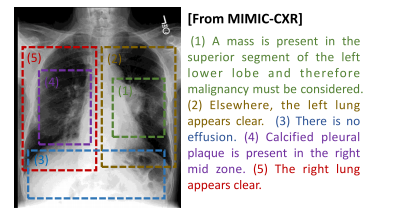

Fig. 5. Demonstration of multi-scale features of medical image–text pairs. The medicalreport is composed of several sentences, with each sentence focusing on region-levelfeatures instead of global-level features. Sentences are independent of each other, andhold different levels of significance.

图5:医学图像-文本对的多尺度特征示例。医学报告由若干句子组成,每一个句子关注的是区域层面的特征,而非全局层面的特征。这些句子相互独立,并且具有不同程度的重要性。